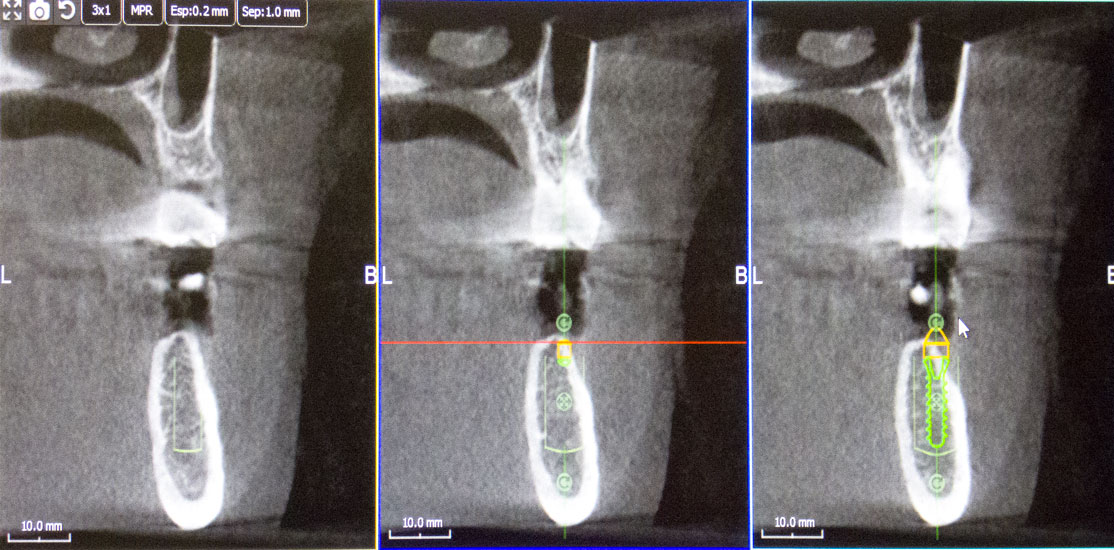

Con este Scaner obtenemos imágenes tridimensionales de la región bucofacial, dientes, hueso maxilar y mandibular, zona sinusal, etc.,  permitiéndonos evaluar con gran precisión el estado del paciente que acude a nuestra consulta, realizando un diagnóstico preciso, que nos posibilita estructurar el mejor tratamiento en cada circunstancia, evitando falsas expectativas y la frustración que conlleva el fracaso de tratamientos inadecuados por su errónea planificación.

La información  aportada por la tecnología 3D nos permite la realización de técnicas innovadoras de regeneración ósea guiada con coágulo del propio paciente, en zonas de gran pérdida de hueso, produciendo resultados altamente predecibles que nos facilitan restaurar la función masticatoria y estética, que los tratamientos convencionales no consiguen.

Las imágenes obtenidas mediante tecnología 3D, nos aportan información fiable de la zona bucodental que requiere tratamiento quirúrgico o conservador, minimizando en gran medida las complicaciones que pueden producirse si no disponemos de ella.